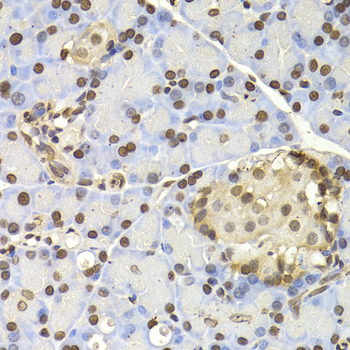

• A2769: image 3

Immunohistochemistry of paraffin-embedded rat pancreas using NAP1L1 antibody at dilution of 1:200 (400x lens).